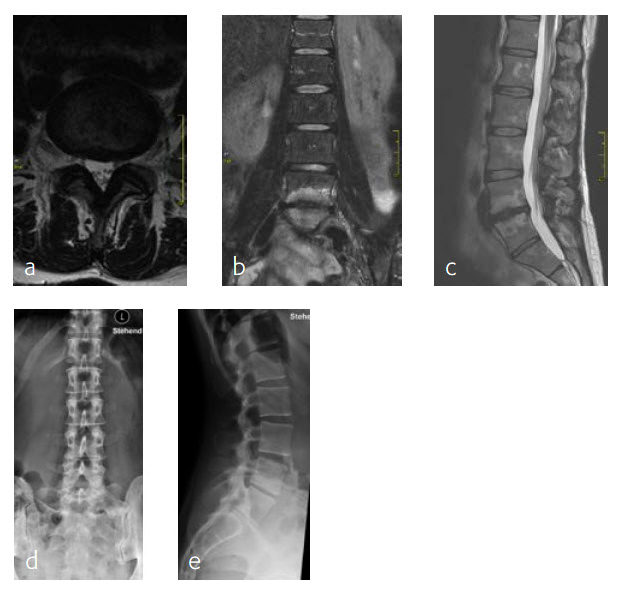

6-month follow-up

By the planned 6-month follow-up, the patient was pain free and fully active. Evaluation with CT scans was undertaken, consolidation was starting (Fig 8).